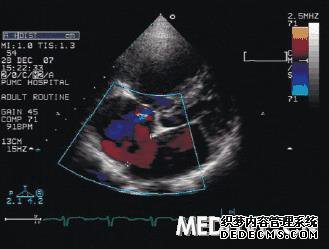

心脏彩色多普勒检查没有问题。我是否需要再次